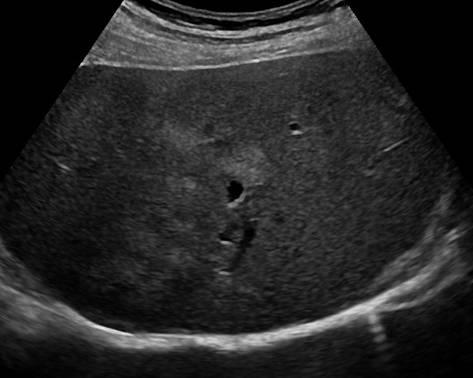

Gan nhiễm mỡ

» Thông tin: Nam giới – 42 tuổi.

» Lâm sàng: Kiểm tra sức khỏe.